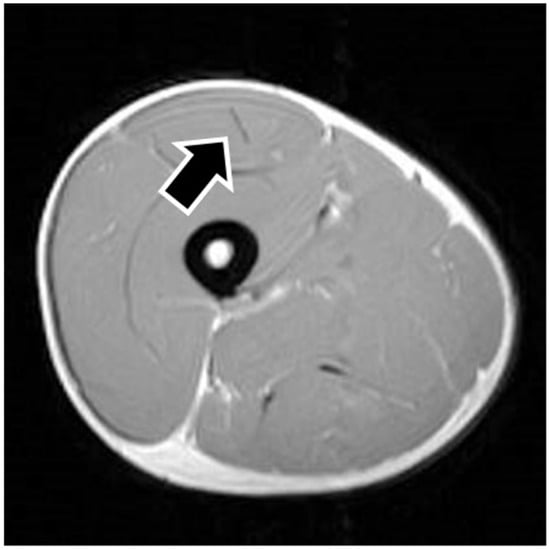

MRI findings are shown in Table 1. In eight of the RF strain injuries, a low signal area was noted in the central tendon (Figure 2). In four of the RF strain injuries, a low signal area was noted in the myofascial junction of the RF (Figure 3). In four of the RF strain injuries, the axial T1-weighted image did not show a low signal (Figure 4). The longitudinal range of the injured region in the 12 RF that showed a low signal area in MRI was approximately 8.8 cm (range, 4–17 cm). When the injured part was limited to the central tendon, the longitudinal range of the injured region was approximately 10.5 cm (range, 5–17 cm).

Figure 4. Noninjured rectus femoris muscle. The figure shows an example of noninjured rectus femoris muscle. The axial T1-weighted image does not show a low signal in the central tendon (black arrow).